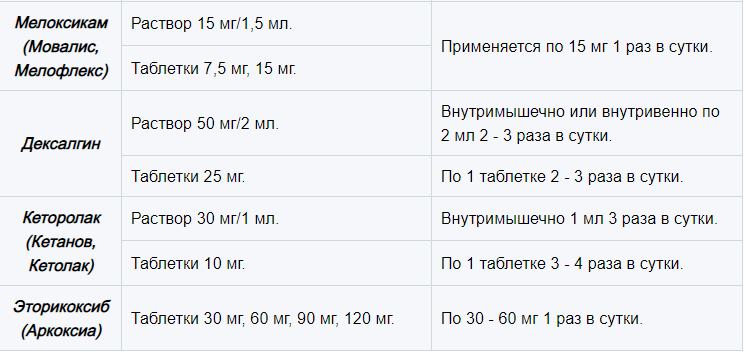

Артроз голеностопного сустава 2 степени схема лечения